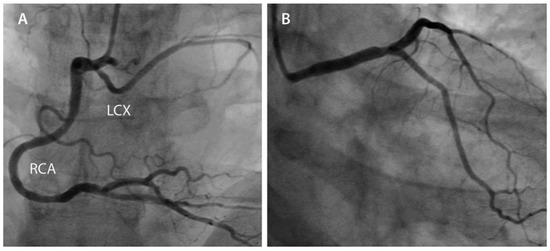

Left Main Stem Thrombosis in a 37-Year-Old Man

by Stéphane Noble, Caroline Frangos and Marco Roffi

A 37-year-old man, with active smoking and dyslipidemia as cardiovascular risk factors, presented with acute anterior ST segment elevation myocardial infarction. Emergent coronary angiography demonstrated a left main coronary artery occlusion. Following primary percutaneous coronary intervention, the patient survived and was free of [...] Read more.

A 37-year-old man, with active smoking and dyslipidemia as cardiovascular risk factors, presented with acute anterior ST segment elevation myocardial infarction. Emergent coronary angiography demonstrated a left main coronary artery occlusion. Following primary percutaneous coronary intervention, the patient survived and was free of symptoms at the one-year followup. Full article

Figure 1